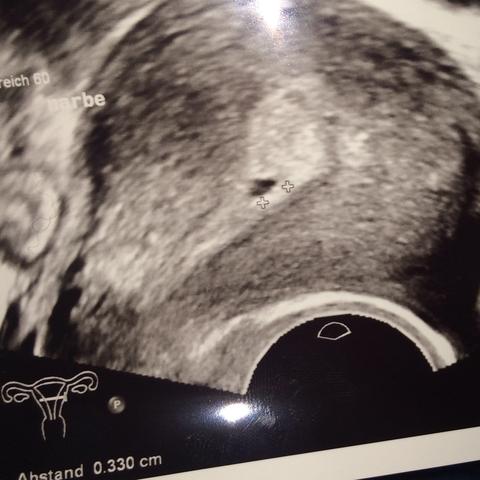

Ich denke das da die Fruchthöhle wächst ist ein sehr gutes Zeichen das sie SS intakt ist !.

Kein Herzschlag in 8 ssw Kein Herzschlag in 8 ssw lauserin am 1910 Hallo, ich muss mir heute den Frust von Seele schreiben Wurde nach meiner ersten IVF schwanger Bis zur 7 Woche ist unser Krümelchen noch brav gewachsen Heute hatte ich wieder Ultraschall Leider ist unser Kleines von letzter auf diese Woche nicht gewachsen. Seien Sie aber unbesorgt, falls Sie in der 7 SSW keine Anzeichen verspüren Wahrscheinlich gehören Sie dann einfach zu den Glücklichen, die Ihre Schwangerschaft ganz beschwerdefrei von Anfang an genießen können Sollten Sie sich dennoch Sorgen machen, vereinbaren Sie ganz einfach einen Termin bei Ihrem Gynäkologen 7. (man sieht es etwas rechts im Bild) In der 7 SSW kann man bereits den Herzschlag des Embryos erkennen Der Herzschlag ist ein wichtiger Faktor, an dem man die Entwicklung 7 SSW Herzschlag und Entwicklung.